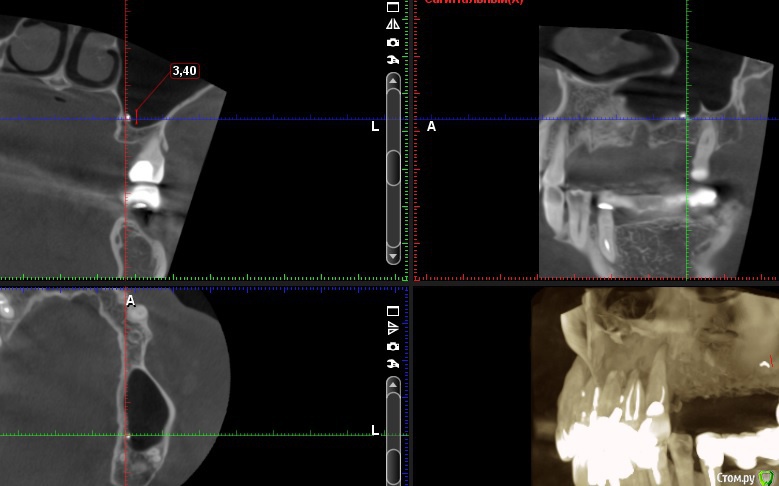

Andre_ Опубликовано 10 февраля, 2016 Поделиться Опубликовано 10 февраля, 2016 (изменено) Извиняюсь за археологию. Планирую синус и поагументировать, возможно, "похудевший" альвеолярный отросток, и тут на КЛКТ подарочек. Удаление при царе Горохе, беспокойств никаких, ЛОР- анамнез спокойный. Отслаиваться нужно прямо там, где лежит. Стоит вообще париться, или не столь существенно? Изменено 10 февраля, 2016 пользователем Andre_ Ссылка на комментарий

StomV Опубликовано 10 февраля, 2016 Поделиться Опубликовано 10 февраля, 2016 Я думаю не стоит, сам по себе мвтериал как правило инертен,а вот если инфецируется,тогда вызывает воспалительные изменения,здесь вме чисто со сторны синуса. Ссылка на комментарий

Andre_ Опубликовано 13 февраля, 2016 Поделиться Опубликовано 13 февраля, 2016 Поздно пить боржом всё соперировалось, судя по контрольной ОПТГ - материал подпаян к шнейдеровой, поднят вместе с мембраной. Визуально, как ни мыл - ничего не различил в ране. Будем посмотреть. Ссылка на комментарий